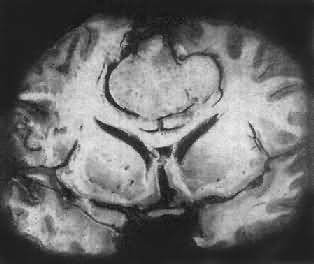

一、中枢神经肿瘤(一)胶质瘤 胶质瘤(glioma)具有特异的不同于其它部位肿瘤的生物学特性: (1)良恶性的相对性:无论高度分化或低度分化的胶质瘤均呈浸润性生长,更无包膜形成。生长迅速、间变程度高的肿瘤,与周围组织截然不同,故边界往往较清楚。 第三脑室分化良好的幼年型星形胶质细胞瘤,由于位于手术禁区,无法进行切除。因此预后不佳。 (2)局部浸润:胶质瘤的浸润性生长主要累及血管周围间隙、软脑膜、室管膜、神经纤维束间。 (3)转移:①脑脊液转移是颅内肿瘤常见的转移方式,相当于颅外恶性肿瘤细胞的淋巴道浸润和转移,特别是位于脑室旁、脑池旁的肿瘤发生这种转移的机会更多。②颅外转移极少见,其中80%以上均有颅脑外科手术史。 1.星形胶质细胞瘤(astrocytoma) 本瘤约占颅内肿瘤的30%,占神经胶质瘤的70%以上。男性较多见。最近研究表明该肿瘤中原癌基因sis有过度表达,erb-B1则有放大。 肉眼观,肿瘤为数厘米的结节至巨大块状。分化较好的肿瘤,境界不清;而分化程度较低的肿瘤则境界分明。瘤体灰白色。质地视肿瘤内胶质纤维多少而异,或硬、或软、或呈胶冻状外观,并可形成大小不等的囊腔。由于肿瘤的生长、占位和邻近脑细胞的肿胀,脑的原有结构因受挤压而扭曲变形(图16-23)。

图16-23 星形胶质细胞瘤 左大脑半球肿胀,肿瘤边界不清,部分呈胶冻状 镜下,肿瘤细胞形态多样,可相似于纤维型星形胶质细胞、原浆型星形胶质细胞和肥胖星形胶质细胞,故分别称为纤维型、原浆型和肥胖型星形胶质细胞瘤。前二者为良性肿瘤,后者性质介于良恶性之间。如肿瘤细胞出现间变,细胞密度增大,异型性明显,核深染,出现核分裂像,毛细血管内皮细胞增生,则为间变性星形胶质细胞瘤,为恶性肿瘤。 高度恶性的星形胶质细胞瘤称为多形性胶质母细胞瘤(glioblastoma multiforme),多见于成人。肿瘤好发于额叶、颞叶白质,浸润范围广,常可穿过胼胝体到对侧,呈蝴蝶状生长(图16-24)。瘤体因常有出血坏死而呈红褐色。镜下,细胞密集,异型性明显,可见怪异的单核或多核瘤巨细胞。出血坏死明显,是其区别于间变性星形胶质细胞瘤的特征。毛细血管明显增生,内皮细胞增生、肿大,可导致管腔闭塞和血栓形成。肿瘤发展迅速,预后极差,患者多在2年内死亡。